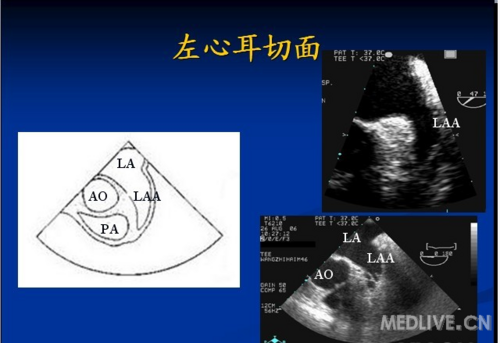

经食道超声心动图----常用标准切面_圈子_医脉通